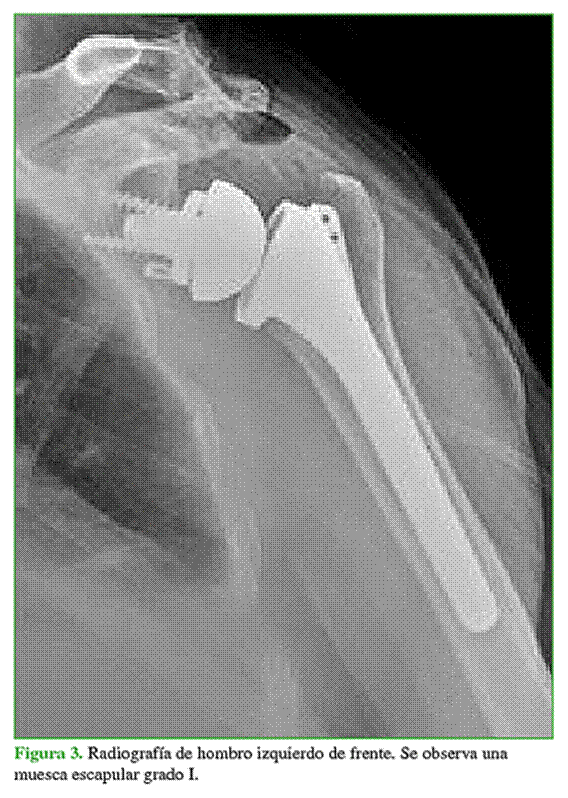

La tasa de complicaciones fue del 12,5% (5 casos). Cuatro fueron intraoperatorias (2 complicaciones menores y 2 mayores). Dos complicaciones menores (5%) fueron una fractura glenoidea que requirió la colocación de una glena de revisión en el mismo acto quirúrgico, sin que esto afectara el resultado obtenido. Una paciente sufrió dos complicaciones mayores. Se trató de uno de los primeros casos de nuestro Centro, en el comienzo de la curva de aprendizaje. La paciente sufrió una fractura periprotésica intraoperatoria de la diáfisis humeral, sintetizada con cerclajes y tratada con un brace, que evolucionó con neuropraxia del nervio radial y resolución parcial. Otra paciente evolucionó con un cuadro de insuficiencia acromial, debido a una fragilización acromial preoperatoria que repercutió en el rango de movilidad (Figura 2).

En las radiografías, se detectó que dos pacientes tenían muescas glenoideas grado I (Figura 3). No hubo casos de aflojamiento del componente humeral, sí se registró como única complicación mayor posoperatoria el aflojamiento mecánico del componente glenoideo en un paciente a los 14 meses de la cirugía inicial; en este caso, se procedió a la revisión con colocación de una glena de revisión (Figura 4). La tasa de supervivencia del implante fue del 97,5%.